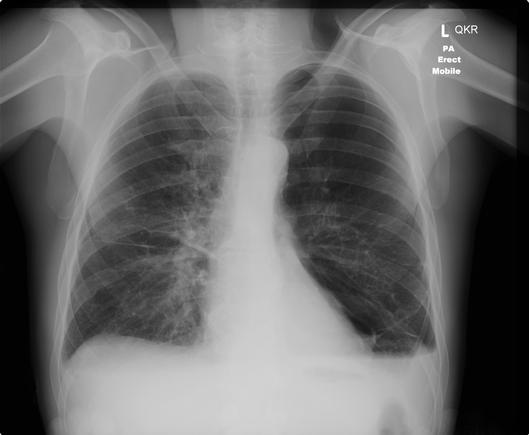

A critically ill 45 year old woman is intubated in the ICU. A procedure is performed and the following test is conducted

What was the procedure?